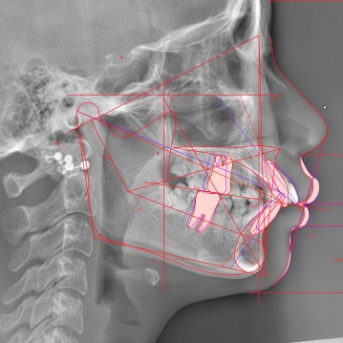

かみ合わせだけでなく、美しい横顔やスマイルラインなども考慮した上で、最適の治療をご提案しています。

2精密検査・治療計画の作成

歯ならび・噛み合わせを詳細に分析し、あなただけの治療計画を作成します。

矯正治療においてもっとも重要なのは「正確な診断」です。